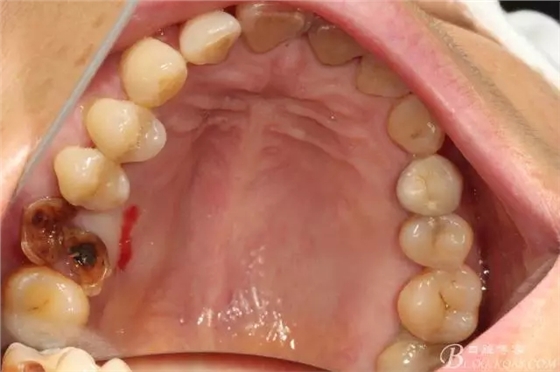

先26號(hào)牙位拔牙前照片顯示牙根頰舌向已經(jīng)裂開

拔牙后拔牙窩里面大量肉芽組織